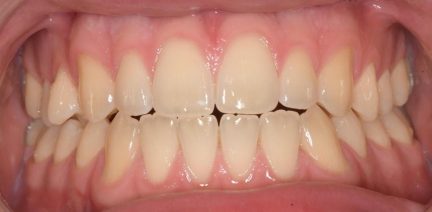

Résultats obtenus

- Relation de classe I obtenue

- -Relation de classe I maintenue

- Guidage fonctionnel des canines des deux côtés

- Articulé antérieur corrigé

- Articulé postérieur corrigé

- Surplomb et recouvrement normaux obtenus

- Lignes médianes coïncidentes

- Bonne inclinaison axiale des incisives

- Courbe de Spee nivelée

- Arches alignées et coordonnées

- Alignement des deux arcades par dérotation

- Forme de l'arcade améliorée

État final